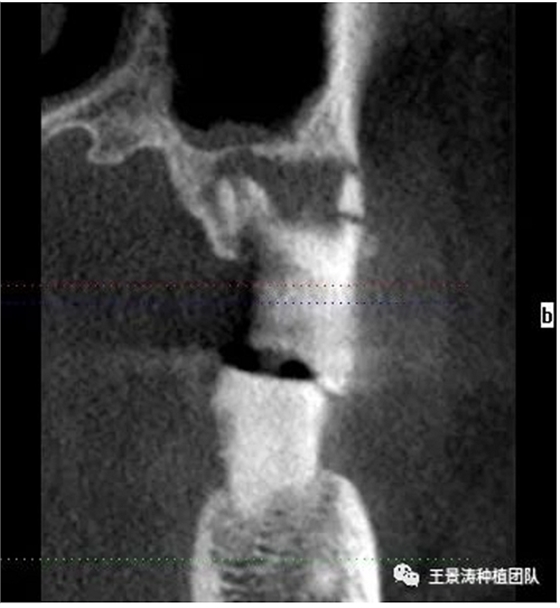

下述病例則是15區(qū)域的即刻種植,15因牙冠折斷于齦下,無法樁核冠修復(fù),則考慮種植修復(fù)。但拍攝CBCT后發(fā)現(xiàn)根尖距上頜竇底距離較短?;颊邽槟贻p女性,無全身系統(tǒng)疾病且可利用上頜竇底與根尖皮質(zhì)骨雙側(cè)皮質(zhì)骨固位,且此位置可通過頰側(cè)軟組織減張技術(shù)獲得嚴(yán)密封閉牙槽窩。因其根尖距上頜竇距離較低,遂拔除15后行上頜竇內(nèi)提升,埋入式種植,最終修復(fù)的完成。

患者左側(cè)16慢性根尖周炎,17缺失。16根尖炎癥距上頜竇底較近,需內(nèi)提升,但是因?yàn)閮?nèi)提升后骨質(zhì)較薄所致植入深度過深,埋入式植入。17非埋入式種植。后期效果均可。